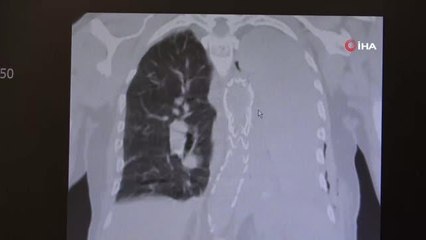

Çağın hastalığı beraberinde psikolojik sorunları getiriyor